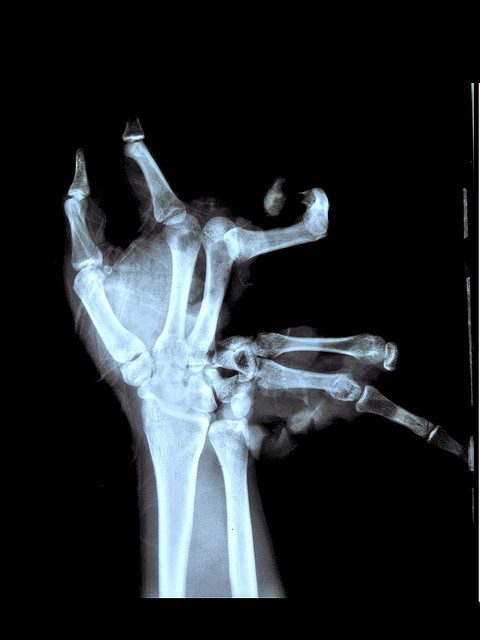

Скорее всего во вселенной мы не одни, просто инопланетяне мастерски прячутся от нас, потому что глядя на то, что вытворяют люди, вы на их месте тоже бы не захотели с собой знакомиться. Например, глядя на эту коллекцию рентгеновских снимков, создаётся ощущение, что у многих людей напрочь отсутствует мозг и инстинкт самосохранения.

Нам остается только догадываться, в каких ситуациях побывали «рентген-модели», но навряд ли они будут их вспоминать долгими вечерами за бокалом вина.

Это… больно!